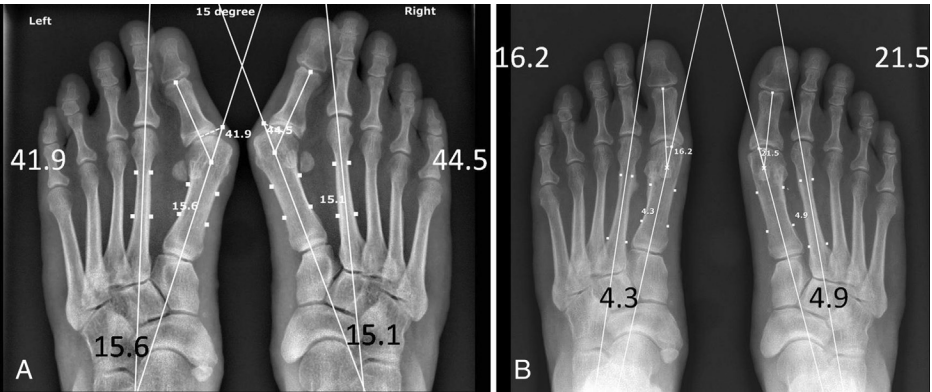

▲图示(A)54 岁女性患者术前站立位 X 线片示:双足存在典型且无合并症的第一序列三联畸形,即拇外翻、第一跖骨内翻及跖籽分离,畸形程度为中度;术前美国足踝外科协会(AOFAS)拇趾评分为双足均 70 分。(B)术后 3 年站立位 X 线片示:拇趾、第一跖骨及籽骨复位满意,双足 AOFAS 拇趾评分均达 100 分。

▲图示(A)64 岁女性患者术前站立位 X 线片示:双足重度第一跖骨内翻,跖趾关节(白色实心箭头)与跖楔关节(白边黑色箭头)对位不良,跖籽分离(黑色实心箭头),且右足第二跖趾关节背侧脱位;术前美国足踝外科协会(AOFAS)拇趾评分 55 分。(B)术后 2 年站立位 X 线片示:第一跖骨间间隙缩小,跖趾关节与跖楔关节对位恢复正常,跖籽关系恢复正常,右足第二跖趾关节脱位减轻;左足 AOFAS 拇趾评分 100 分,右足 93 分;双足足趾跖趾关节角分别为 15.9° 和 25.0°,跖骨间角分别为 4.3° 和 4.7°。